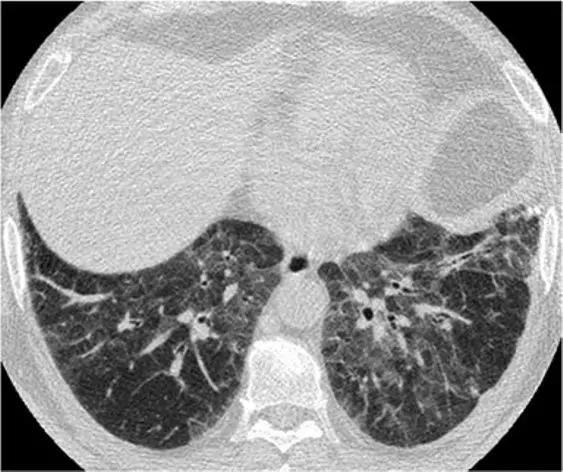

5、磨玻璃影-网状影混杂模式

有时,在肺部同一区域中可能同时存在磨玻璃样影和网状影共存,这种组合几乎等同于不可逆的纤维化。典型疾病:是非特异性间质性肺炎(NSIP)。表现为磨玻璃影改变为主、轻度网状改变。鉴别疾病:硬皮病、特发性肺纤维化(IPF)和脱屑性间质性肺炎(DIP)。

单纯的脱皮性间质性肺炎(DIP)是罕见的,但其最常见的模式是磨玻璃样改变伴有轻度网状改变,能类似于NSIP,通常没有蜂窝状改变(图22)。可能有助于鉴别诊断的细微CT特征是存在可能代表肺气肿的小微囊肿(因为患者几乎总是吸烟者),支气管扩张或肺泡管扩张(无明显的蜂窝状纤维化)。

*DIP 患者HRCT的下叶水平显示出混合的“磨玻璃样改变伴轻度网状结构”。无蜂窝样改变